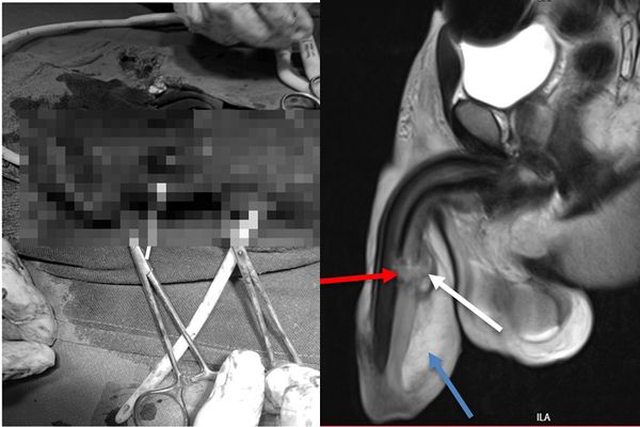

▲男子陰莖出現3處撕裂傷。(圖/翻攝自IJSCR)

他緊急就醫後才發現,原來他的陰莖有3處斷裂,醫生表示,他的陰莖膨脹扭曲,有嚴重

內出血,且尿道已持續出血5小時。

雖然陰莖並沒有骨頭,但睪丸白膜和海綿體嚴重撕裂的狀況,讓陰莖形同骨折,而該名男

子有3個嚴重撕裂處,醫生也緊急開刀處理。

這起案例被記錄在《國際外科病例報告期刊》(IJSCR)中,主治醫師Bartholomeo

Nicholaus Ngowi表示,手術過程病患感到強烈疼痛,所幸後來修復完成,目前該名男子

經過休養後,性生活已恢復正常。